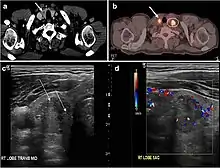

Fig. 8. A 48-year-old male patient post total thyroidectomy with PTC recurrence. a Transverse greyscale ultrasound of the neck demonstrates a left thyroid bed heterogeneous, predominantly hypoechoic irregular lesion with calcifications (white arrow). b A spot image of iodine 123 total body scan of the neck demonstrate a focus of abnormal radiotracer uptake at the left thyroid bed (Black arrows) between the annotated markers. c Enhanced axial CT scan of the neck demonstrates an enhancing large left thyroid bed mass (white arrow) with no calcifications. The lesion exerts a mass effect on the oesophagus (black arrow) and is inseparable from the trachea.[1]

Fig. 9. A 58-year-old male patient with persistence PTC at thyroid bed with hypervascular nodal metastasis. a–c Transverse greyscale and colour Doppler neck ultrasound demonstrate hypoehoic soft tissue in the left thyroid bed (white arrow in a). There are a heterogeneous enlarged lymph nodes at level 2 and 3 with markedly increased vascularity (white arrow in b and c). d–f Enhanced axial CT images of the neck demonstrate a 2.7 × 1.4 cm hypodense soft tissue lesion anterior to the left carotid sheath (white arrow). There are left-sided enhancing abnormal and enlarged lymph nodes at cervical level 2 and 3 (black arrows).[1]